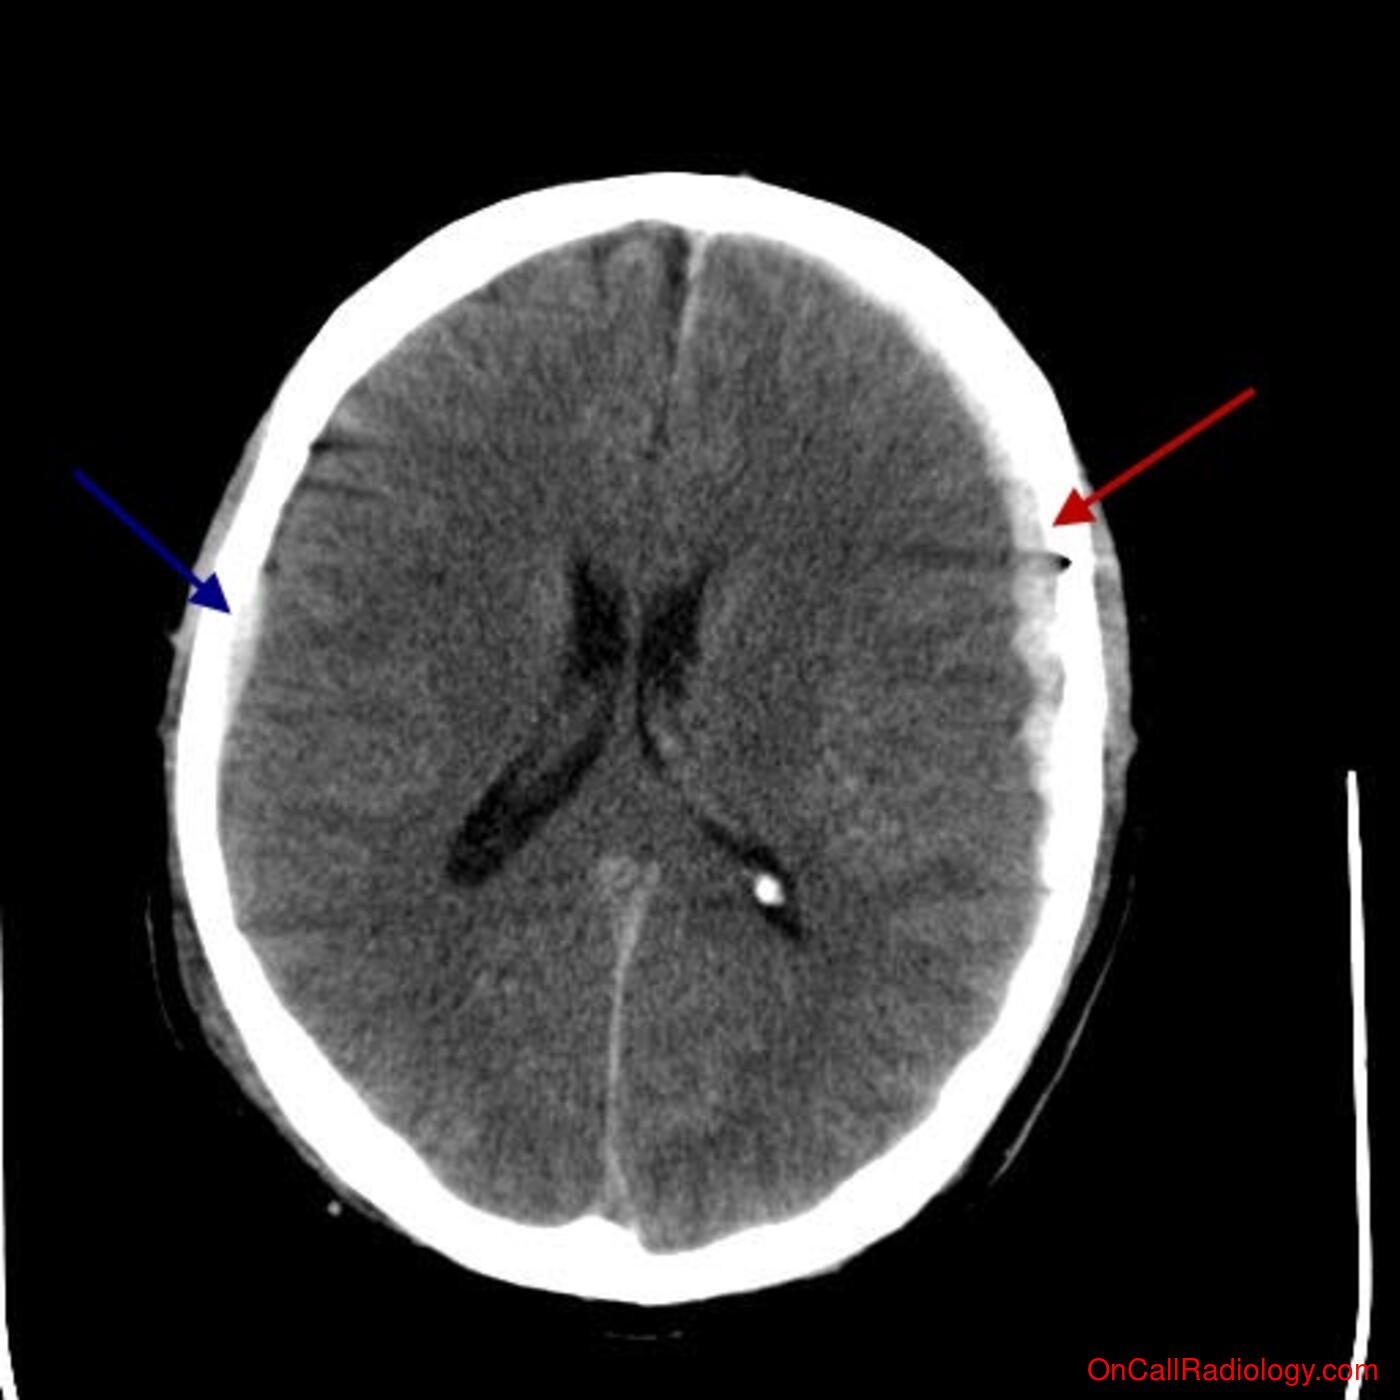

Parietal Scalp Hematoma

No loc, vomiting or decreased gcs. Head ct confirmed left parietal skull fracture with smear.

It usually results from traumatic tearing of the bridging veins that cross the subdural. Subdural hematoma is a bleeding between the inner layer of the dura mater and the arachnoid mater of the meninges. The diagnosis is generally clinical, with a fluctuant boggy mass developing over the scalp (especially over the occiput) with superficial skin bruising.

Sharply demarcated soft tissue density.

Subgaleal hemorrhage or hematoma is bleeding in the potential space between the skull periosteum and the scalp galea aponeurosis. Scalp hematomas in this age group maybe the only sign of traumatic brain injury (tbi). Hematomas are a collection of blood outside of a blood vessel. An unusual presentation of valproic acid toxicity. Bilateral symmetrical parietal extradural hematoma. Subgaleal hemorrhage or hematoma is bleeding in the potential space between the skull periosteum and the scalp galea aponeurosis. It usually results from traumatic tearing of the bridging veins that cross the subdural. A scalp hematoma means there is a collection of blood under the skin of the what do you mean by: Risk of traumatic brain injuries in children younger than 24 months with isolated scalp hematomas. Keywords craniocerebral trauma, scalp, hematoma, infant, skull fracture. Usually over parietal bones, then occipital, and lastly frontal. Hematomas or hematomata) commonly occurs either following a perinatal injury at delivery or as part of head trauma. There are several types of hematomas, which are often described by their location (for example, under the fingernail, in the liver. The diagnosis is generally clinical, with a fluctuant boggy mass developing over the scalp (especially over the occiput) with superficial skin bruising. Subdural hematoma is a bleeding between the inner layer of the dura mater and the arachnoid mater of the meninges. No bruising has appeared other than the swelling soft mushy area the size of an average half xxxxxxx i m trying to put up. Parietal foramina are small defects in the superoposterior angles of the parietal bones through the clot may form fibrous tissue, with calcification beginning at the periphery of the hematoma.12 with.